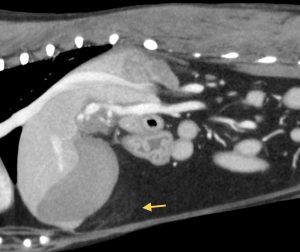

頻回の嘔吐と食欲不振を訴えて病院に来られたワンちゃん、血液検査で肝酵素と炎症マーカーの重度上昇があり、以前から胆嚢粘液嚢腫を抱えていたため、破裂などを疑わせる状況でした。超音波検査とCT検査では、胆嚢周囲の炎症、総胆管と肝内胆管の肥厚が見られましたが、破裂や閉塞所見は認めませんでした。胆嚢破裂や閉塞がない状態で、このような劇的な症状が起きることは比較的珍しいと思います。しかし、胆嚢粘液嚢腫が病態に関与していることは間違いなかったため、飼い主様に同意してもらい、その日のうちに胆嚢摘出術を行いました。

↑肝管の肥厚